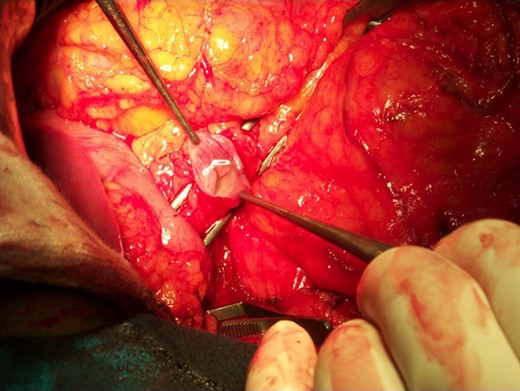

At duodenotomy, we actually found a 2 × 3 cm lesion of the pancreatic head, infiltrating the medial wall of the duodenum cephalad to the papilla of Vater, that was not be amenable to a limited resection. We therefore diverted to a duodenocefalopancreasectomy with pyloric preservation according to Traverso–Longmire.

The operative specimen showed a normal thin choledocus (incannulated with a probe) cephalad to a fragile inhomogeneous area corresponding to the tumor (Fig. 4) and an enormously dilated pancreatic duct (held by the forceps) (Fig. 5).

The operative specimen showing a normal thin choledocus (incannulated with a probe) cephalad to the tumor.